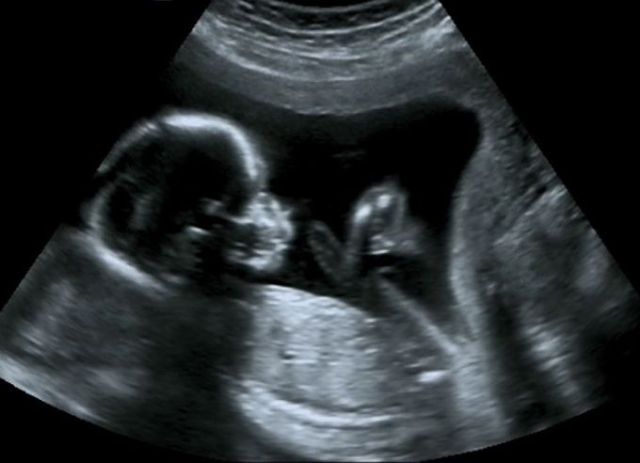

B超检查既能对胎盘定位、羊水测量,又能对单胎多胎、胎儿发育情况及有否畸形和葡萄胎等作出早期诊断。超声是人人皆知的医学检查,是医生们非常重要的诊病工具。

第二次B超检查一般安排在妊娠中期(怀孕20周左右),此时宫内羊水相对较多,胎儿大小比较适中,宫内有较大的活动空间,对B超检查来说,有较好的对比度,可以清晰地看到胎儿各个器官。较明显的畸形,如先天性心脏病,无脑儿,脑积水,脊柱裂,腹壁缺损,四肢短小,多囊肾,消化道闭锁等容易被发现。如果有必要,可以及时进行治疗或终止妊娠。